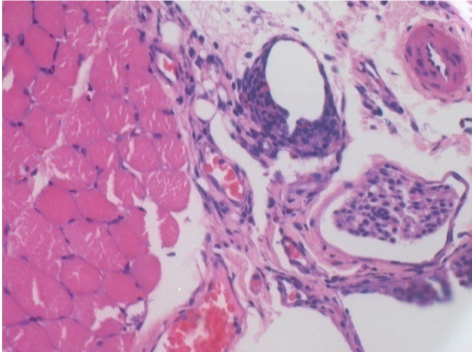

10 días después de la inyección de Endopeel

10 días después de la inyección de Endopeel 0,1 ml en el músculo pretibial derecho.

Aquí puede ver la formación de las vacuolas que están rodeadas de linfocitos. Las vacuolas son diferentes a la necrosis tisular. La presencia de linfocitos está relacionada con la permeabilidad de las membranas celulares.

L : Control-100xD10

R:100xD10

R :200xD10

R :400xD10